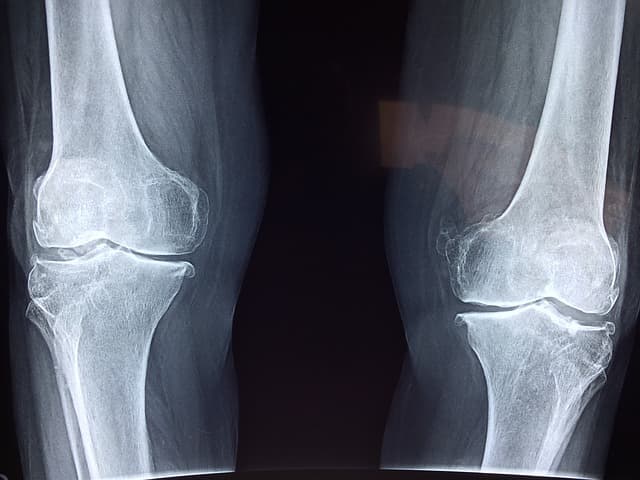

골다공증은 뼈의 밀도가 낮아지고 뼈가 약해지거나 뼛속이 비는 것을 말하는데요. 나이가 들어가면서 서서히 오기도 하고 가족력이나 골절로 인해 골다공증이 나이보다 일찍 나타나는 사람도 있습니다. 골다공증의 여러 원인과 증상에 대해서 알아보고 미리예방할 수 있는 골다공증에 좋은 음식 4가지도 추천해 드리겠습니다.

골다공증은 뼈의 밀도가 감소하여 뼈가 약해지는 건데요.

그 증상은 서서히 진행되기 때문에

금방 티가 나는 것이 아니고

골절이 생기면 이미 골다공증이 진행 된거라고 합니다.

골밀도 검사는 방사선을 이용해서 수치를 확인할 수 있는데요.

0을 정상치로 두었을 때 골다공증 수치를 정리해 보겠습니다.

사람의 뼈는 오래된 뼈는 소실되고

새로운 뼈가 만들어지면서 골밀도를 유지하게 되는데요.

나이가 들면 오래된 뼈는 계속 소실되는데

새로운 뼈는 생성되는 속도가 현저하게 줄어들어

빈자리가 채워지지 않게 되어 골밀도가 점차 떨어지게 됩니다.